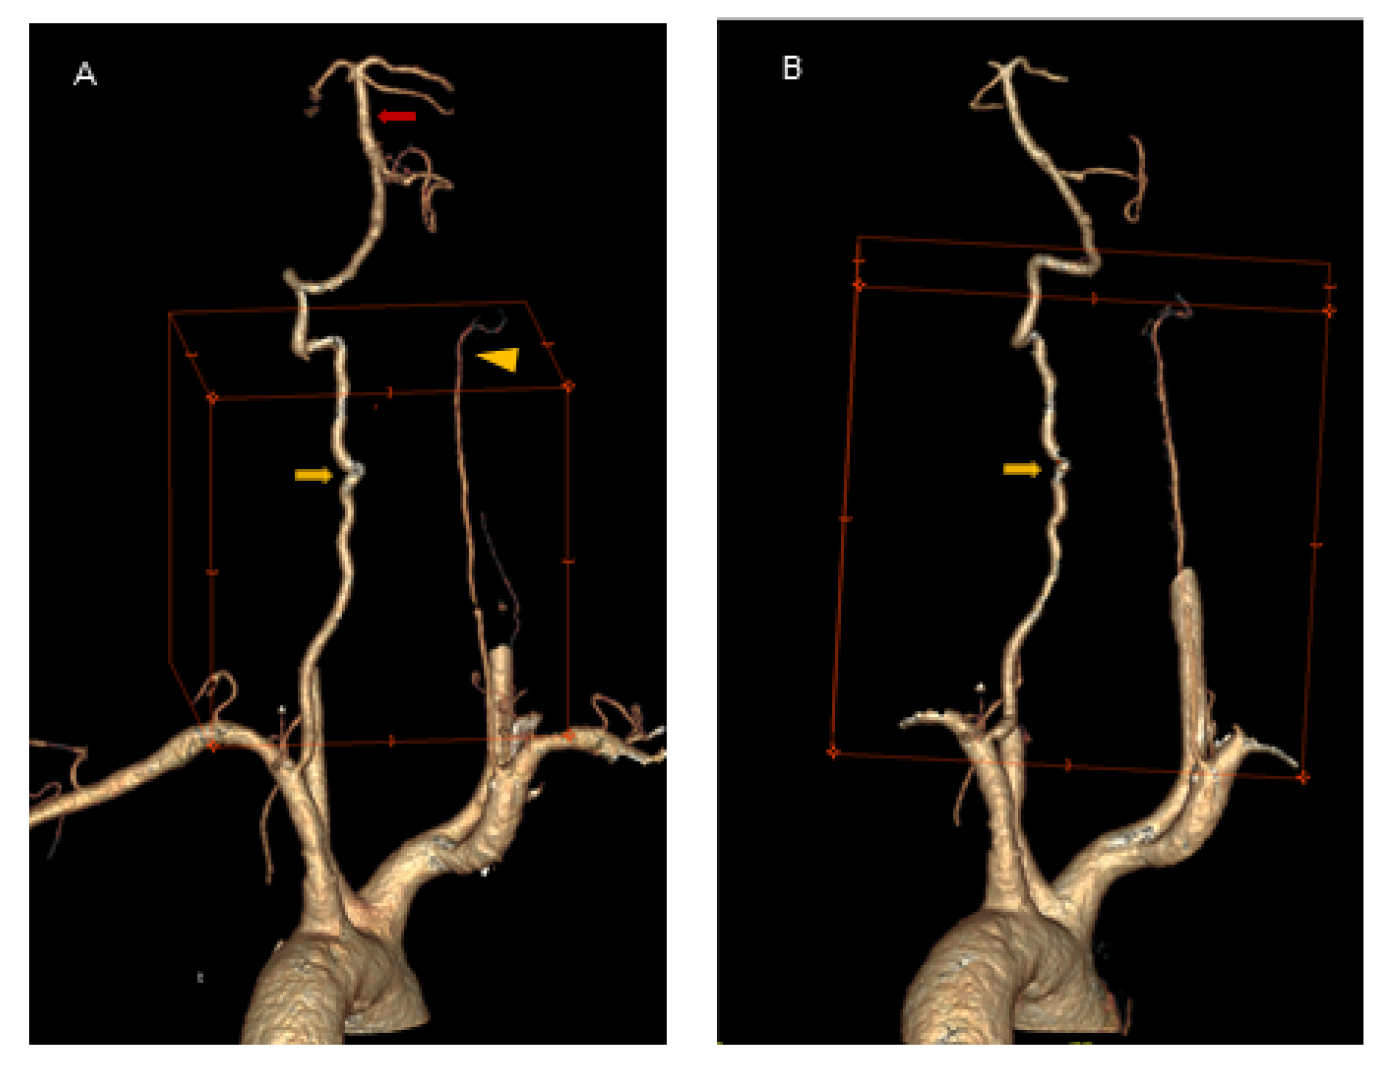

Doppler ultrasonography (USGD) of cervical vessels was performed in the neutral position and in left-side rotation of the head. In the neutral position of the head, USGD detected right vertebral artery (R-VA) hypoplasia (width: 1.8 mm; N < 2–3 mm) [6] with an increased blood flow resistance (PSV/EDV = 28/0 cm/s; RI = 1) (Figure 1A). Flow velocity in L-VA in this position was normal (Figure 1B). Moreover, in the internal carotid arteries (ICA), atheromatous plaques up to 1.7 mm thick were detected, yet no significant stenosis was found. During left-side rotation of the head, flow velocity in L-VA significantly declined (from 111/35 cm/s to 20/7 cm/s; RI dropped from 0.69 to 0.64) (Figure 1C) behind a certain point (at C4 level), where a turbulent flow with increased up to 200 cm/s peek systolic velocity was observed (Figure 1D. No flow abnormalities in R-VA were revealed during right-side rotation (Figure 1E).

Figure 1. USGD in the neutral, left and right-side head rotations. Panel (A): USGD in the neutral position of the head demonstrates R-VA hypoplasia (width: 1.8 mm; N < 2–3 mm) with an increased blood flow resistance (PSV/EDV = 28/0 cm/s; RI = 1) (white arrow). Panel (B): USGD in the neutral position of the head demonstrates normal flow velocity in L-VA. Panel (C): USGD in left-side head rotation demonstrates post-stenotic flow velocity decline in L-VA (from 111/35 cm/s in neutral position to 20/7 cm/s in rotation; RI drop from 0.69 to 0.64)—the tardus and parvus wave (white arrowhead). Panel (D): USGD in left-side head rotation demonstrates a turbulent flow in L-VA with increased up to 200 cm/s peek systolic velocity at C4 level (red arrow). Panel (E): USGD in right-side head rotation demonstrates no changes in the blood flow.